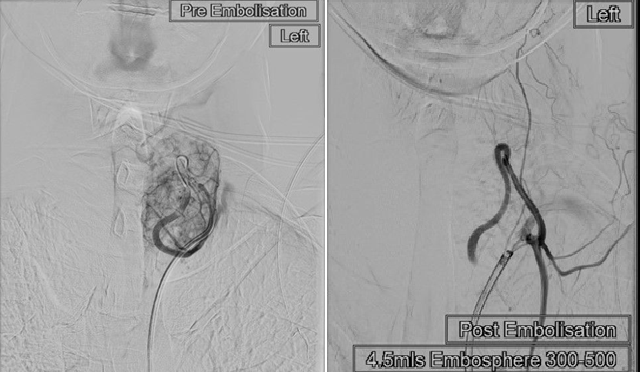

This month we undertook the UKs first thyroid artery embolisation (TAE) as part of the TArGET study to assess this new minimally invasive option to treat large thyroid nodules. This provides a non-surgical option for patients who are not candidates for, or who wish to avoid traditional surgery or radioactive iodine. The procedure is performed under local anaesthesia, as an outpatient, allowing patients to go home the same day. Recovery is quick, with most patients returning to normal activities within one to two days.

The first procedure was successfully undertaken this month in the University Department of Radiology at the Royal Berkshire NHS Foundation Trust. The research team is being led by Dr Farhan Ahmad, in collaboration with Dr Amelia Hollywood at University of Reading, Dr Yan Li at Oxford University Hospital and Dr Theingi Aung, Mr Sid Nagala and Prof. Mark Little at Royal Berkshire Hospital.